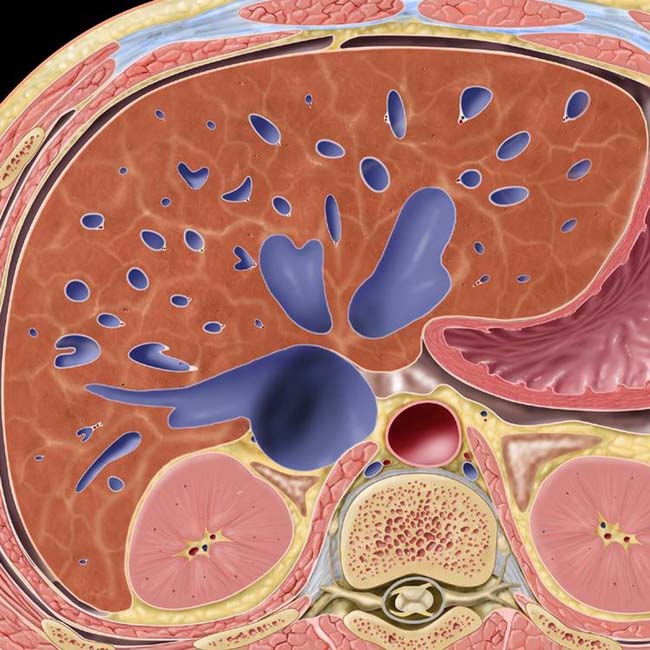

In day to day clinical practice, combined liver and heart dysfunction coexist due to complex cardiohepatic interaction. Passive hepatic congestion is caused by stasis of blood within the liver parenchyma due to compromise of hepatic venous drainage. Congestive hepatopathy refers to liver damage caused by a variety of cardiovascular conditions that trigger passive venous congestion in the liver. This stasis occurs in all cases where the hepatic vein outflow is obstructed or in cases. The effective management of the patients is ensured after. Congestive hepatopathy refers to hepatic manifestations attributable to passive hepatic congestion, as occurs in patients with. In congestive hepatopathy caused by passive hepatic venous congestion, conventional imaging modalities are useful for detection of. Passive hepatic congestion is caused by stasis of circulating blood within the liver parenchyma.

Passive Congestion Radio . Passive hepatic congestion is caused by stasis of circulating blood within the liver parenchyma. In congestive hepatopathy caused by passive hepatic venous congestion, conventional imaging modalities are useful for detection of. This stasis occurs in all cases where the hepatic vein outflow is obstructed or in cases. In day to day clinical practice, combined liver and heart dysfunction coexist due to complex cardiohepatic interaction. The effective management of the patients is ensured after. Passive hepatic congestion is caused by stasis of blood within the liver parenchyma due to compromise of hepatic venous drainage. Congestive hepatopathy refers to liver damage caused by a variety of cardiovascular conditions that trigger passive venous congestion in the liver. Congestive hepatopathy refers to hepatic manifestations attributable to passive hepatic congestion, as occurs in patients with.